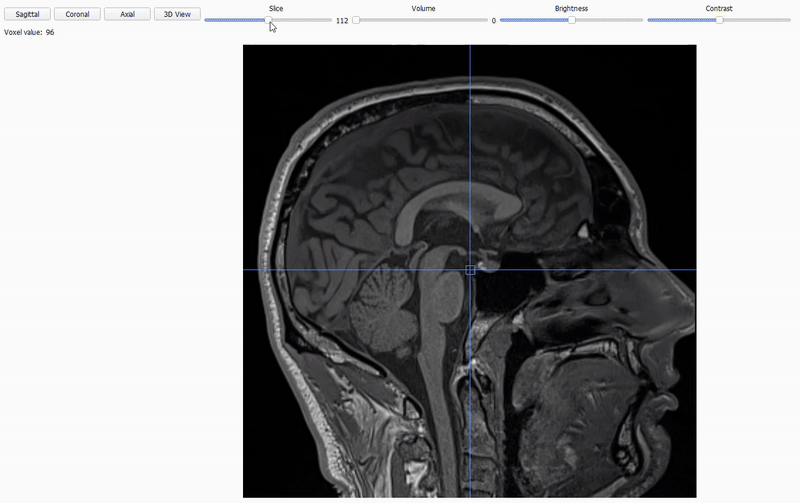

Sequence type view: BIDSplorer can open NIfTI images (.nii/.nii.gz) across different sequence types (anat, func, fmap, dwi). Use the different option to

Inspect the three orthogonal planes with the

Axial,CoronalandSagittalbuttons.

Scroll through the 2D cross-sections of the current plane with the

Slicestoggle.

Adjust

brightnessandcontrastto improve visibility.